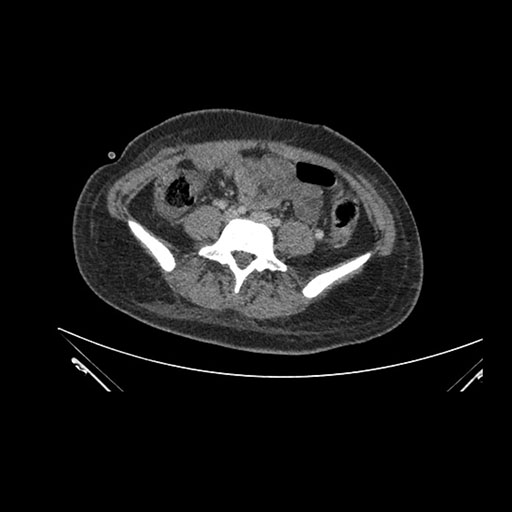

Imaging Analysis

Look through the patient's CT scan to identify any areas of concern for the necessary procedure.

Based on initial findings, which issue(s) would you be most concerned about?